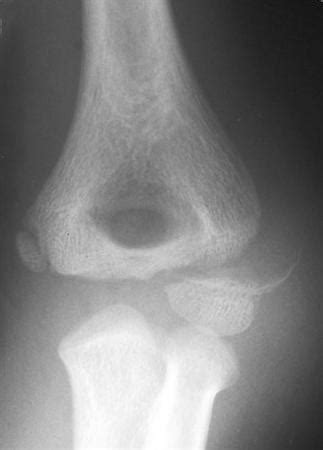

These fractures have been associated with higher energy injuries compared to other elbow fractures. Anteroposterior (a) and lateral (b) views.

On the lateral view, cortical disruption is usually seen posteriorly rather than anteriorly as in supracondylar fractures. Paediatric lateral condyle fractures подробнее. Nondisplaced (<2mm), articular surface intact stage ii:

Pediatric lateral condyle fractures are the second most common fractures in the pediatric elbow and are characterized by a higher risk of nonunion, malunion, and avn than other pediatric elbow fractures. Для просмотра онлайн кликните на видео ⤵. Fracture through the lateral condyle can extend into the capitellum, disturbing the. Staying out of trouble with pediatric elbow fractures _not supracondylar fractures. Fixation of acute lateral condyle fracture подробнее. These fractures have been associated with higher energy injuries compared to other elbow fractures. Pediatric supracondylar fractures and pediatric physeal elbow fractures. Our literature search showed only 2 reports on these concomitant injuries. Original editors ashley bohanan, alisha lopez, hannah duncan, neha palsule, brittany buenteo. Pediatric lateral condyle fractures and medial epicondyle fractures are uncommon; Fractures of the lateral condylar physis that exit through the capitellum should be treated with the same indications as a milch ii fracture with emphasis placed on achieving and maintaining articular congruity until healed by closed or more often open means. Incidence 17% of all distal humerus fractures in the pediatric population, 2nd most common elbow fracture (after. Ossification centers of the elbow. Haematological conditions programme effectively manage your patients with different. Fracture of necessity in child /real story подробнее. Second most common fracture pattern about the elbow in pediatrics. Upper limb fractures become common in children soon after they become ambulatory.